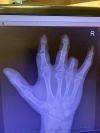

Zdar borci tak ruka vypadá že se docela zotavuje.

I přes boje v nemocnici odvedli dobrou práci a snad se chytne i ukazováček který to má 50 na 50 zatím.

Snad ty umělé klouby co jsem dostal nebudou zlobit a z jara sednu na kolo. Všem dík co mi přáli!

Tak říkal jsem si, že dlouho nepíšeš. Ten ukazováček přitom na první fotce vypadal nejhůř, ale nebylo to odumírání, ale spíš nedostatečný odtok krve. Doufejme, že se chytne, tady to už vypadá podstatně lépe. Oni doktoři jsou opatrní, aby něco slibovali, myslím, že ta naděje bude větší než 50%, Otok a prosakování krve je už pryč, tak snad to vyjde.

0 0